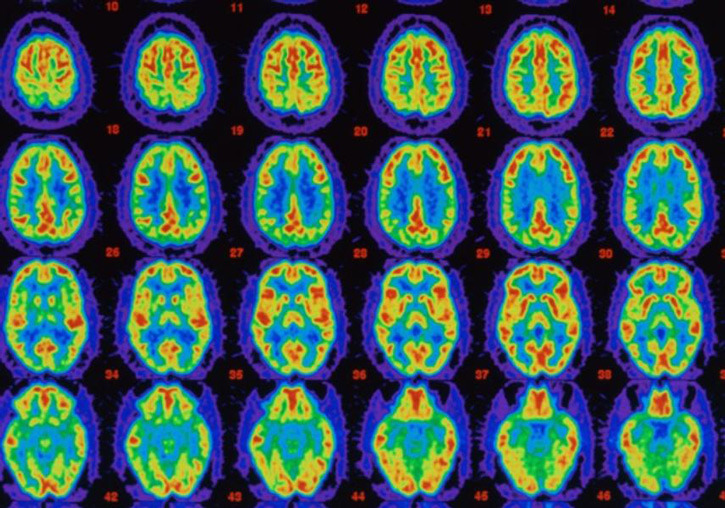

Photo: Courtesy of Health Freedoms. Evidence that Sleep Detoxes the Brain

The researchers discovered that during sleep brain cells contract, increasing the space between the cells by as much as 60 percent, allowing the spinal fluid to wash more freely through the brain tissue. The scientists found that the glymphatic system was almost 10 times more active during sleep than when awake.

The discovery of the self-cleaning brain, coupled with previous research out of Washington Universityshowing that levels of beta-amyloid drop during sleep, could hold keys and clues to the prevention of and treatment for Alzheimer’s disease and dementia.